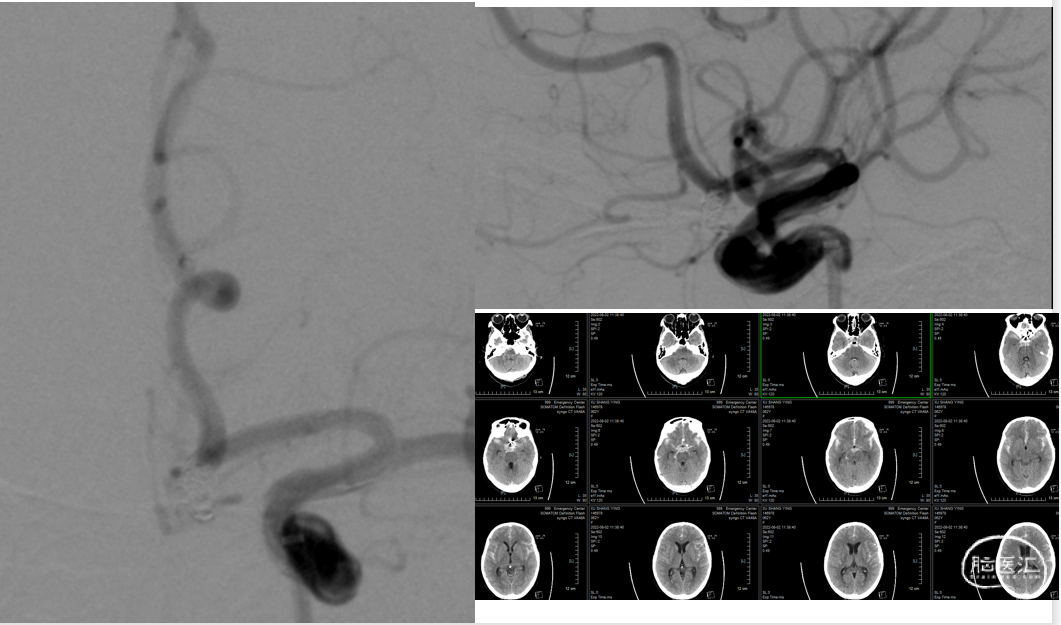

入院头颅CT

入院头颅CTA

压迫左侧颈动脉,行右侧颈内动脉造影示:前交通开放,可见左侧大脑前动脉显影良好。

左侧颈内动脉造影,左侧A1优势。

3D造影可见:前交通动脉可见约5.8mm*4.3mm动脉瘤,瘤颈宽3.5mm,三根大脑前。

在Synchro0.014 200cm微导丝携带下将Echelon-10微导管置于左侧大脑前动脉A2段,另一Echelon-10微导管送至动脉瘤腔内。

沿Echelon-10微导管将5mm*15cm、3mm*8cm、2.5mm*6cm弹簧圈(EV3)送入动脉瘤腔内。

复查造影:动脉瘤栓塞致密,双侧大脑前动脉血流通畅。

沿Echelon-10微导管将3mmx15mm支架(Neuroform Atlas)置入左侧大脑前动脉,复查造影:双侧大脑前动脉血流通畅。

颅内正侧位造影:动脉瘤栓塞致密,双侧大脑前动脉通畅。

左侧造影未见动脉瘤影,右侧路径可。

3D造影可见:前交通动脉可见约5.8mm*4.3mm动脉瘤,瘤颈宽3.5mm。

术后第一天复查头颅CT